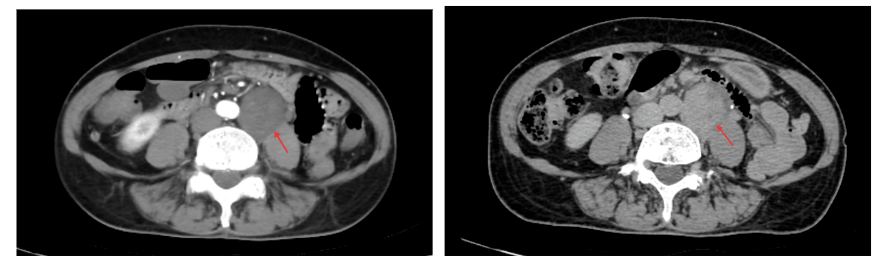

此次接受手术的患者,肿瘤不仅深居腹膜后,更紧贴脊柱腰大肌、输尿管及结肠血管,周围组织毗邻关系错综复杂,手术中稍有不慎便可能损伤重要脏器,采用常规手术方案甚至需面临器官切除的风险,这对手术团队的技术水平和协作能力提出了极高要求。

为确保手术安全顺利开展,建瓯市总医院胃肠外科高度重视,官申副院长与福建省肿瘤医院大肠癌诊治中心杨春康教授线上展开充分的研讨。双方结合患者详细的影像学检查结果,全面梳理病情,反复研判肿瘤浸润范围及与周围组织的解剖关系,精准规划手术路径,最终共同制定了个性化的腹腔镜微创切除方案,明确“精准剥离、完整切除、功能保护”的核心目标,为手术成功奠定了坚实基础。

手术当天,杨春康教授与我院胃肠外科团队默契配合、精准操作。借助腹腔镜高清放大视野,手术团队清晰呈现肿瘤与周围重要组织的毗邻关系,熟练运用腹腔镜微创技术进行精细解剖,在复杂的组织间隙中小心分离、精准剥离,全程规避重要血管与神经,最大限度保护周围正常组织。整个手术过程流畅高效,仅用不到一小时便成功将腹膜后肿瘤完整切除,术中出血少,脊柱腰大肌、输尿管、结肠血管及周围神经肌肉均得到完好保护,圆满达成术前既定目标,成功避免了器官切除对患者生活质量的影响。